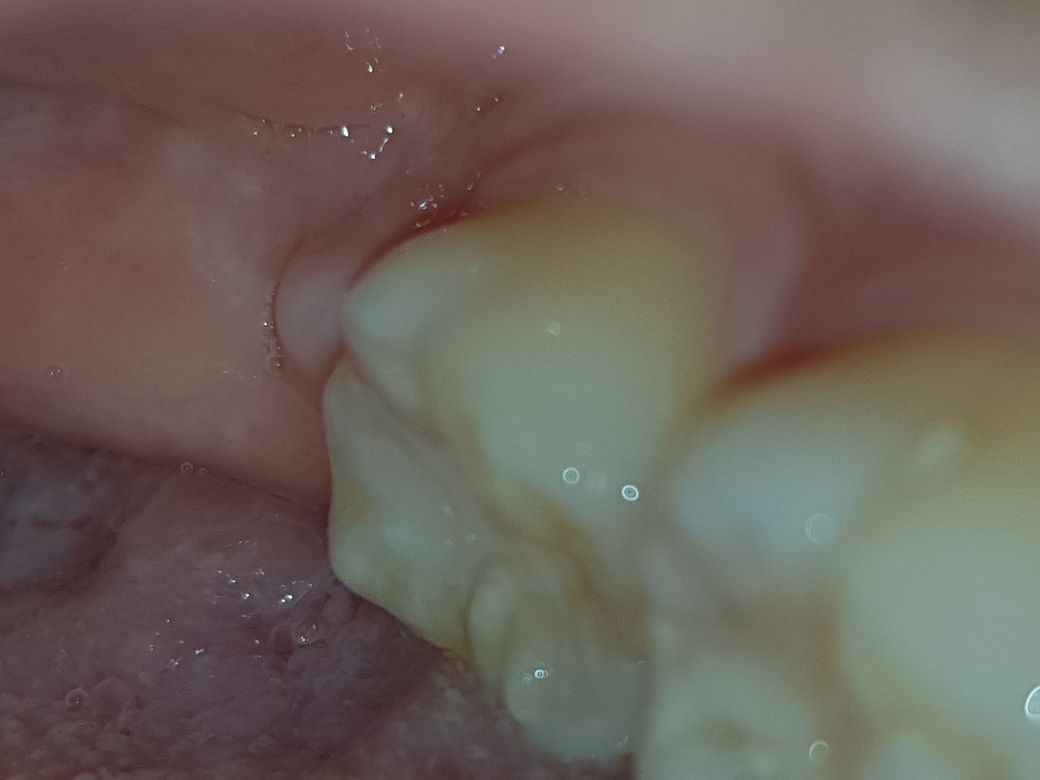

잇몸에 불룩 튀어나온 부분 무엇일까요?

사랑니 뺀지 7달 되었고, 사랑니 4개 다 뺐습니다.

사랑니 있던 잇몸중 한 곳에서만 이런 혹(?)이 생겼습니다.

7달동안 없다가 어제 갑자기 생겼습니다.

이거 염증일까요? 아니면 아무는 과정일까요?ㅜㅜ

7달동안 없다가 갑자기 새살이 튀어나올수도 있나요?ㅜㅜ

염증 소견은 보이지 않습니다. 다만 정확한 진단을 위해서는 방사선 사진이 필요해보입니다. 다만 특별한 문제는 없을 것으로 보이며 단순히 잇몸이 부풀어 올랐을 가능성이 있습니다. 다만 정확한 확진을 위해서는 방사선 사진을 찍어봐야 할 것으로 보이며 치과 방문이 필요합니다.

사진으로만 보았을때는 염증성 병소라기 보다는 생리적 잇몸의 치유양상으로 보이나 통증,발적, 염증성 반응이 있으실 경우 가까운 치과의원이나 발치하신 병원으로 가셔서 문의해보시면 될 듯합니다.

사진으로 봐서는 잇몸이 자라 올라온 것 같네요.

건강한 사람은 잇몸이 잘 자라올라올 때가 있는데 볼록하게 된 것 같네요.

통증이나 다른 증상이 없다면 정상적인 잇몸색이므로 걱정안하셔도 될 것 같습니다.